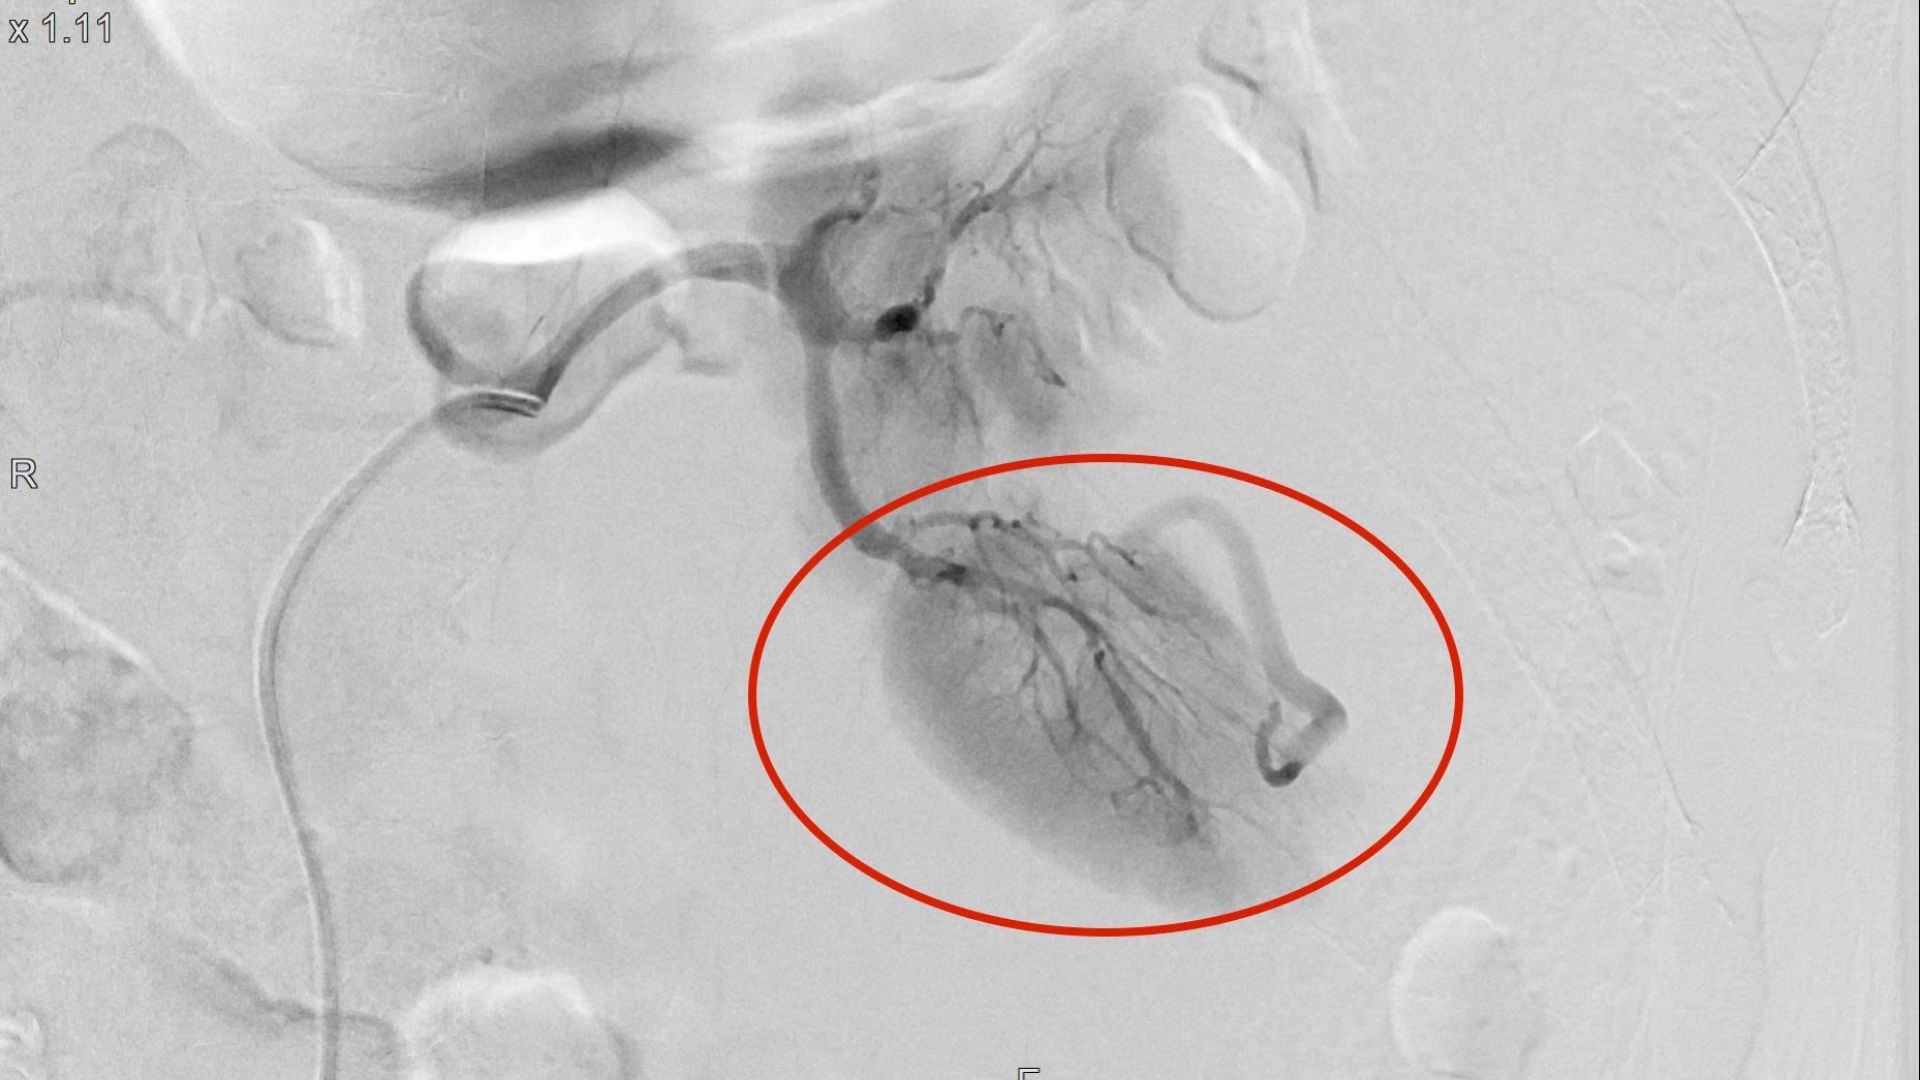

Sau hội chẩn, các bác sĩ xác định bệnh nhân bị vỡ thận trái tự phát mức độ nặng, có ổ chảy máu đang hoạt động. Thay vì mổ hở hoặc cắt bỏ thận - những phương án tiềm ẩn nhiều rủi ro, đặc biệt ở người cao tuổi, ekip quyết định can thiệp mạch cầm máu. Thủ thuật được thực hiện trong khoảng 30 phút, xác định chính xác vị trí thoát mạch tại phân thùy sau thận trái và gây tắc hai nhánh động mạch đang chảy máu. Sau can thiệp, tình trạng đau giảm rõ, huyết động ổn định hơn.